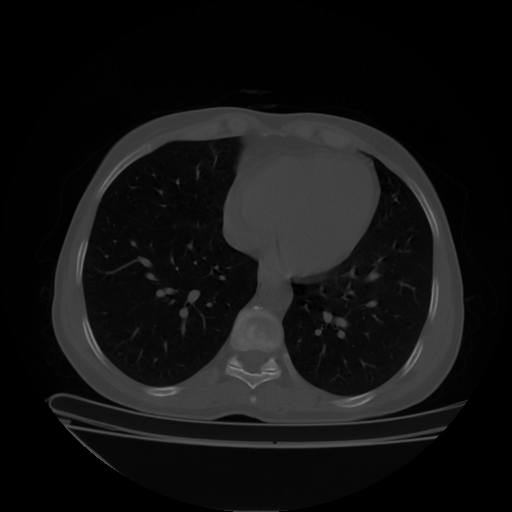

Image Grid

4×3 grid: Rows show different image types (Original NATIVE, Reconstructed NATIVE, Original VENOUS, Generated VENOUS), Columns show windowing techniques (No Window, Lung Window, Mediastinum Window)

Original NATIVE CT scan (input)

No window - Raw intensity values

Original NATIVE CT scan (input)

Lung window (WL -600, WW 1500 → Low −1350, High +150)

Original NATIVE CT scan (input)

Mediastinum window (WL 40, WW 400 → Low −160, High +240)

Windowing Parameters

- No Window: Raw intensity values without windowing

- Lung Window: WL -600, WW 1500 → Low −1350, High +150 (optimal for pulmonary structures)

- Mediastinum Window: WL 40, WW 400 → Low −160, High +240 (optimal for soft tissues)